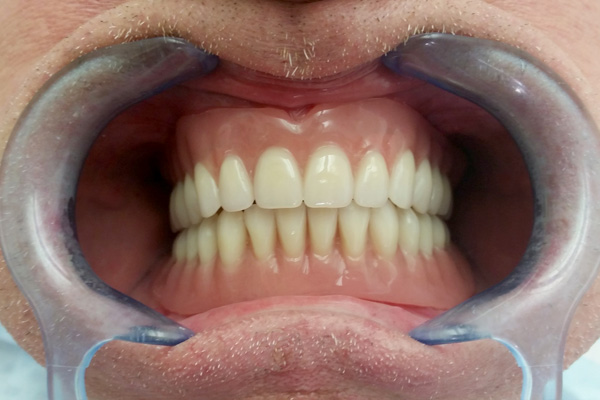

Dentures on implants